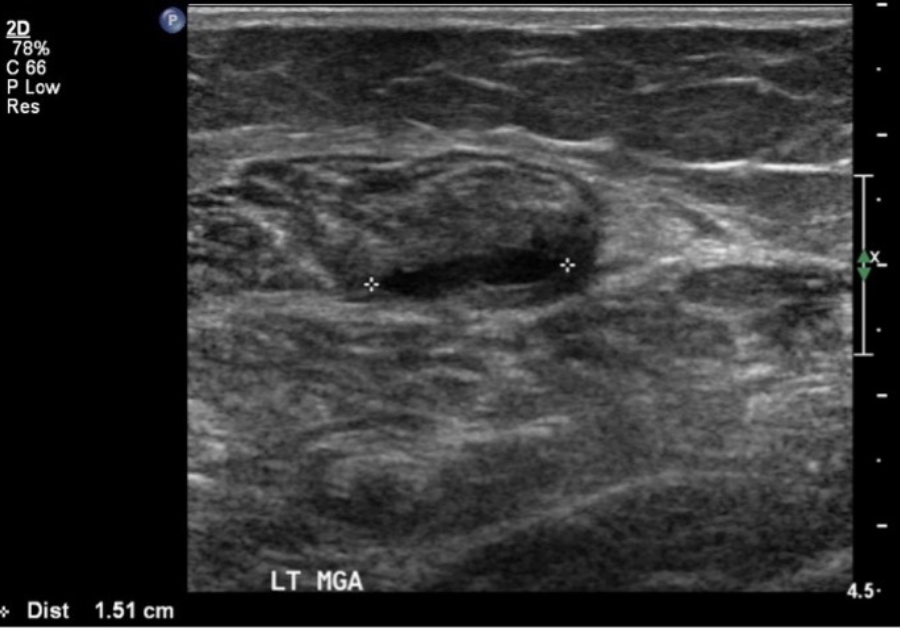

Long and axial views of a medial gastrocnemius muscle tear. Arrow = fluid filling the tear